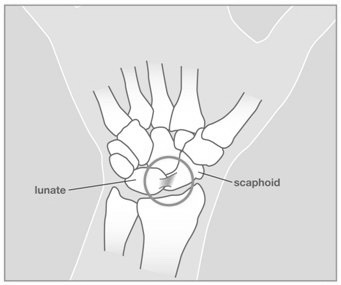

One of the most important and commonly injured ligament in the wrist is the scapholunate ligament. This ligament stabilized the scaphoid bone to the lunate bone. If this ligament is injured it can cause significan dysfunction to the wrist. This injury needs to be recognized and treated appropriately.

This X-ray shows the normal orientation of the bones in the wrist.